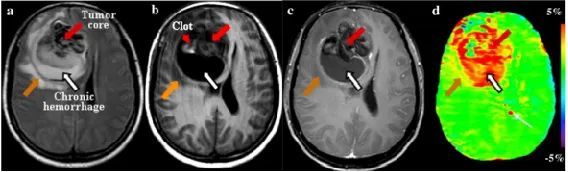

图2 多形性胶质母细胞瘤患者的 MR 图像

a)FLAIR图像示右额叶中异质信号占位。低信号区域可能代表出血。b)T1加权图像示肿瘤大多低信号,小区域高信号强度(红箭头)为出血。c)钆增强T1加权图像示肿瘤核心稍强化(红箭),具有充满慢性出血的不强化囊性腔(白箭)。d)APTw图像示,肿瘤核心(红箭)和囊性腔(白箭)具有较高的APTw信号,而出血灶(红箭头)为低APTw信号。APTw图像上心室附近的红点(细白箭)是伪影。H&E染色脑切片(×50)也证实肿瘤核心(红箭)中存在高密度多形式肿瘤细胞。(WenZ,etal.Neuroimage,2010)